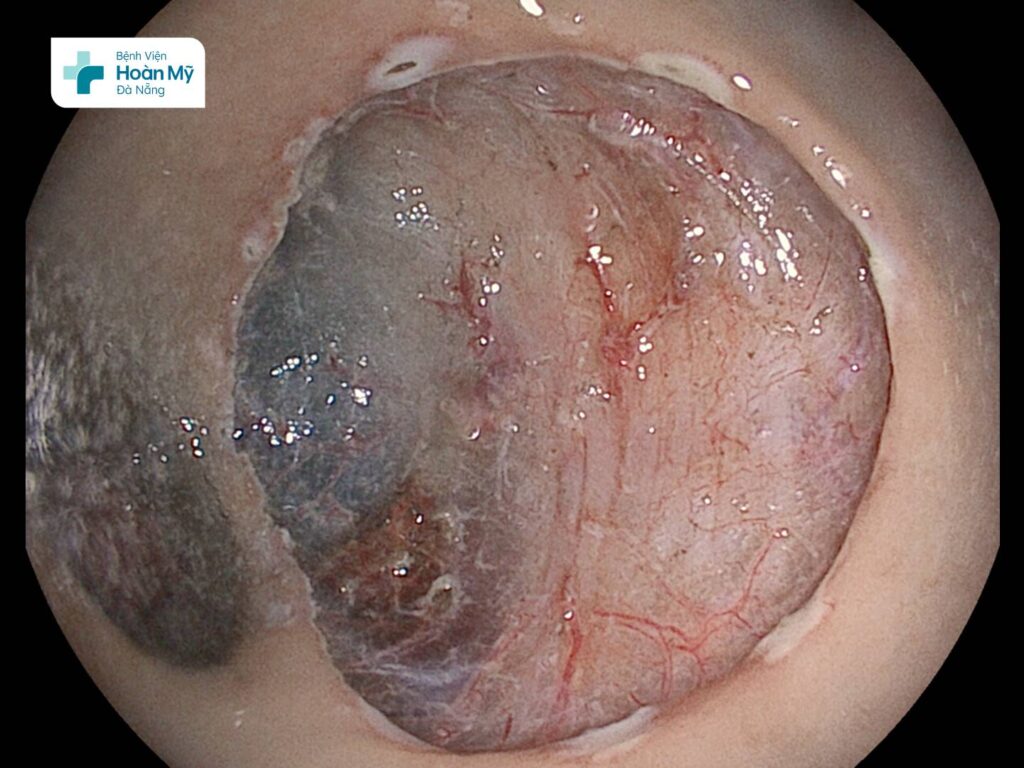

Người bệnh được làm các xét nghiệm cần thiết, chuyên sâu hơn và được tiến hành nội soi cắt tách dưới niêm mạc ESD. Thủ thuật được thực hiện nhanh gọn, an toàn trong 45 phút. Vài giờ sau thủ thuật, ông T đã có thể đi lại, sinh hoạt bình thường mà không đau bụng, không đi cầu ra máu. Hai ngày sau thủ thuật, ông T đã ổn định và có thể xuất viện về nhà.

Tổn thương tiền ung thư trực tràng được cắt tách trọn vẹn mà không ảnh hưởng đến ống tiêu hóa